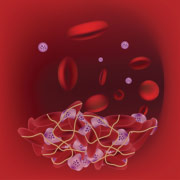

The thrombin generation test

Created in 1953 in Oxford, the thrombin generation test (TGT) is being updated. The TGT is a functional test exploring coagulation in its entirety, thus constituting a modern exploration path of hemostasis.